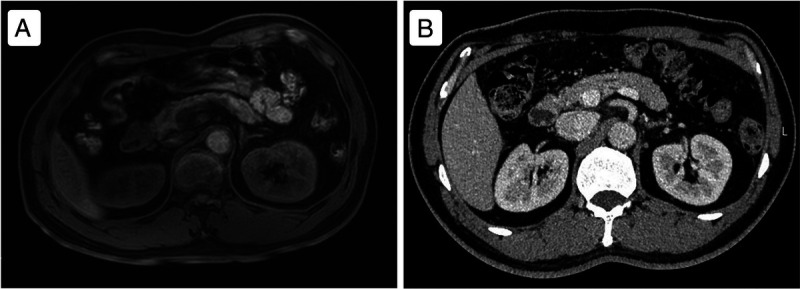

An unusual case of duodenal neuroendocrine tumor presenting with melena diagnosed by EUS-guided fine-needle biopsy.

一例不寻常的十二指肠神经内分泌肿瘤病例,通过胃肠道超声引导下细针活检确诊。